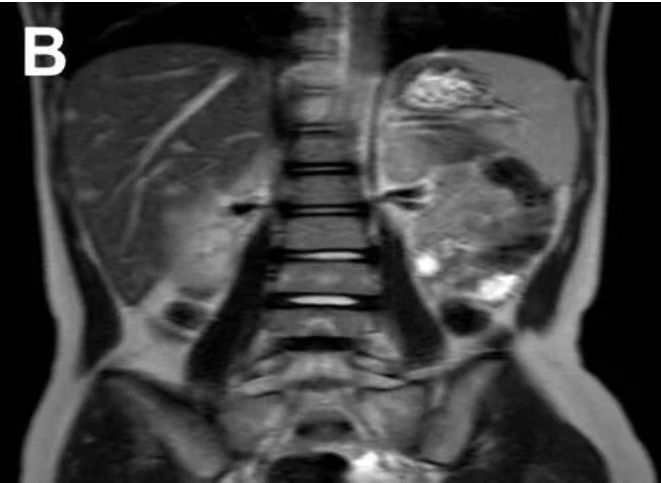

除了反复发热,患儿没有其他症状,但体格检查却发现她的肝脾肿大,左颈部可触及 20 mm*10 mm 大小的淋巴结,同时,外院的 MRI 影像学检查也提示了全身骨骼出现了奇怪的信号改变。

患儿全身 MRI

图源:参考资料 1

出于这样的顾虑,在来到儿童医学中心后,患儿首先由血液科收治入院。随后,B 超显示患儿的肝脏和脾脏多发散在斑片状低回声区,进一步腹部 MRI 显示患儿肝脏、脾脏存在多个不规则信号影。

患儿腹部 MRI

影像学表现让医生再次考虑到恶性肿瘤的可能。